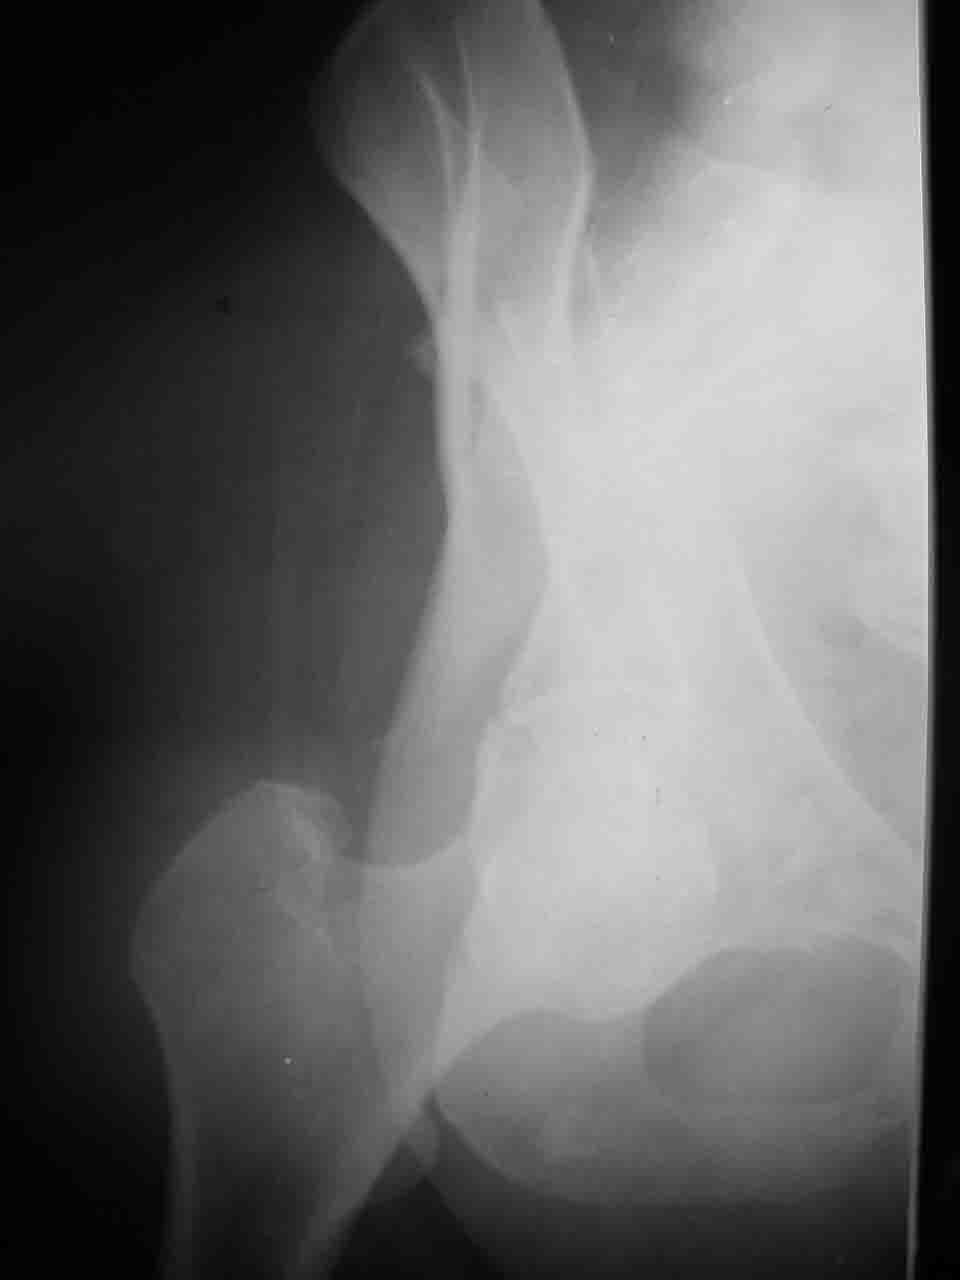

Re: Перелом вертлужной впадины

Снимки и схема